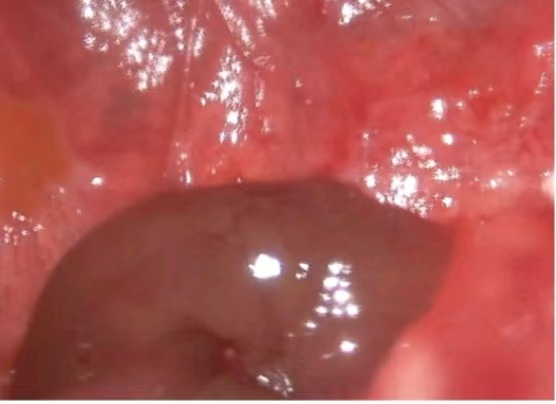

经充分术前准备,胸外科医疗团队为患者行经胸腔镜右侧肺大疱切除术+经胸腔镜胸膜粘连松解术+经胸腔镜脓胸清除术。手术历时约4小时。术中,麻醉科医师凭借丰富经验为手术平稳保驾护航,崔健以精细操作成功规避中转开胸。术中及术后感染的有效防控也避免了胸腔感染及伤口愈合不良的发生,患者最终顺利康复出院。这场对抗复杂肺部疾病的战役中,患者最终成功重获健康,这既得益于胸外科崔健与胸外科医疗团队的精湛治疗与悉心调理,更离不开麻醉科、超声科、放射科及急诊科等兄弟科室的鼎力协作。多学科团队的强力支持,赋予胸外科迎战任何挑战的坚定信心。

▲术中肺大疱内残留脓液

▲脓胸坏死物质与粘连